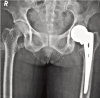

Background and objective: Intracapsular femoral neck fractures are common in the elderly population. To avoid the poor outcome of internal fixation and for early mobilization, hemiarthroplasty is performed. However, there is inadequate evidence to support the choice between unipolar or bipolar hemiarthroplasty. The aim of this study was to compare the outcome of unipolar with the bipolar prosthesis in geriatric patients.

Methods: Forty-one patients above 60 years of age and an acute displaced fracture of the femoral neck were randomly allocated to treatment by either unipolar or bipolar hemiarthroplasty, in the Department of Orthopaedics, between September 2009 and October 2012. Functional outcome was assessed and compared using Harris hip score and radiological parameters with a follow-up of one year.

Results: The two groups of patients with mean age of 67.3 in bipolar group and 75.6 in unipolar group did not differ in their pre-injury characteristics and perioperative parameters. The mean Harris hip score in bipolar and unipolar groups was 86.18±12.18 and 79.79±15.55, respectively (p=0.183); range of motion was 210.63±28.39 and 181.58±37(p=0.015) with bipolar and unipolar groups, respectively. Functional activities were better in the bipolar group. Complications like painful hip, posterior dislocation, periprosthetic fracture and acetabular erosion were encountered in unipolar prostheses.

Conclusion: The use of bipolar endoprosthesis in the management of displaced femoral neck fractures in the elderly was associated with better mean Harris hip score and incidence of complications was limited. Hence, bipolar would be a better option in elderly patients with fracture neck of femur.